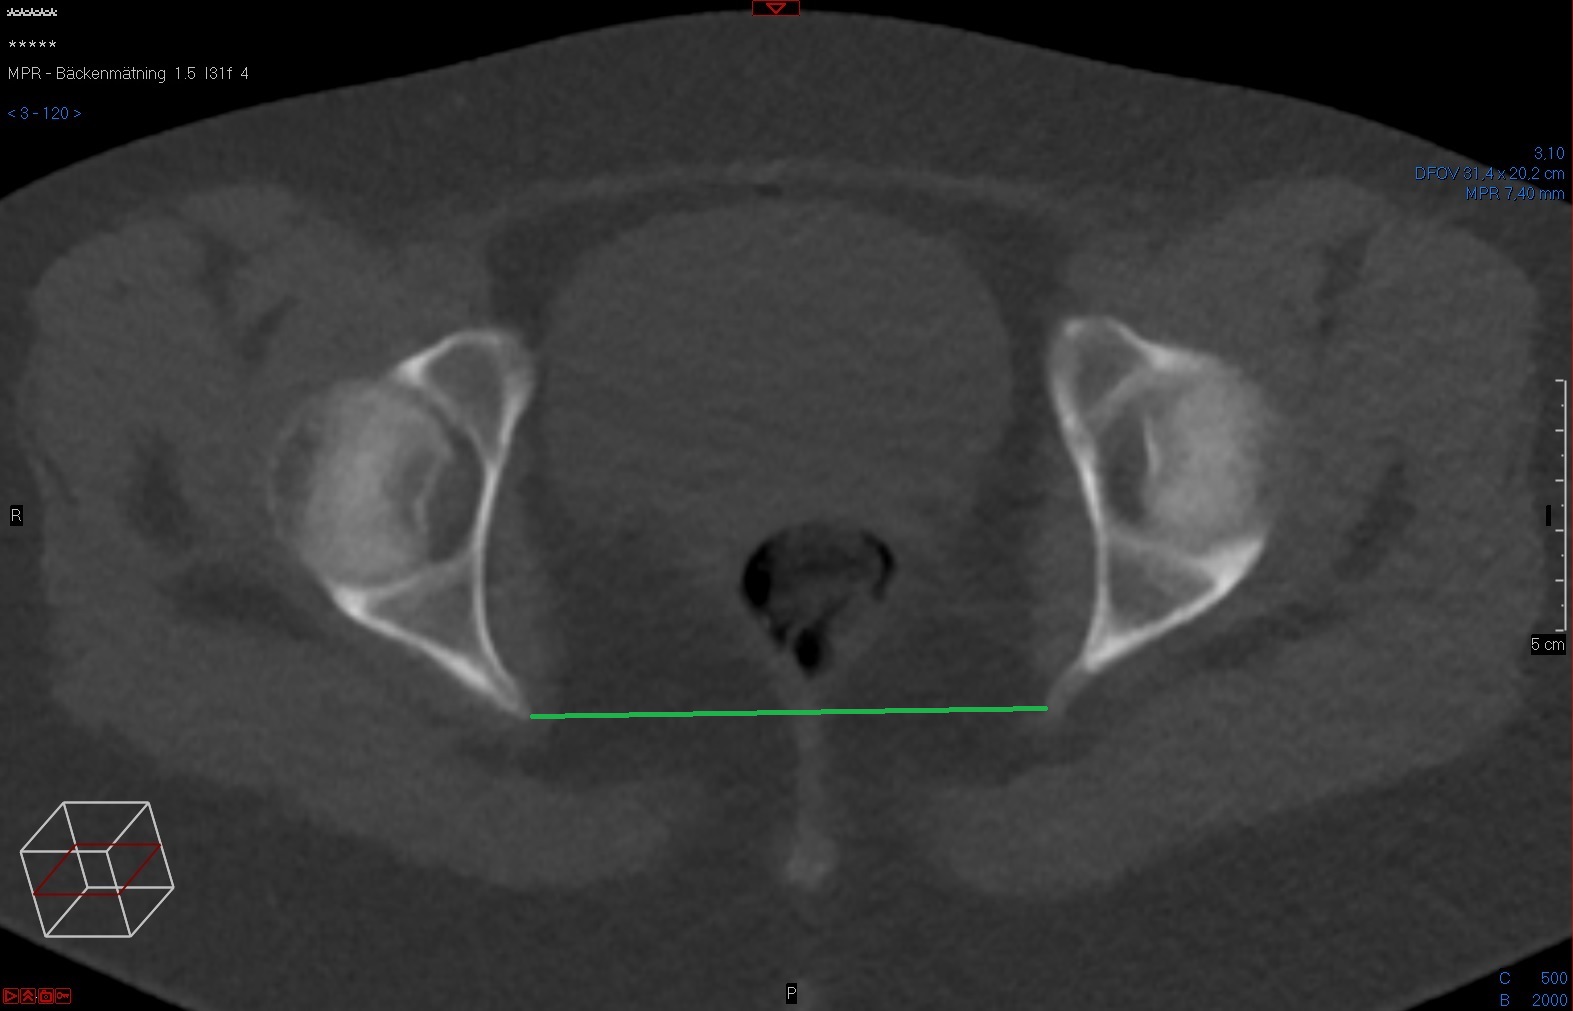

Tunna snitt-serien axialt i Power Viewern ("MPR"), snittjocklek 7-10 mm, skelettfönster. Bekräfta att planet är vinkelrätt mot cristae iliacae (topogrammet kan användas som referens). Scrolla fram till spinae ischiadicae, mät där avståndet är kortast.